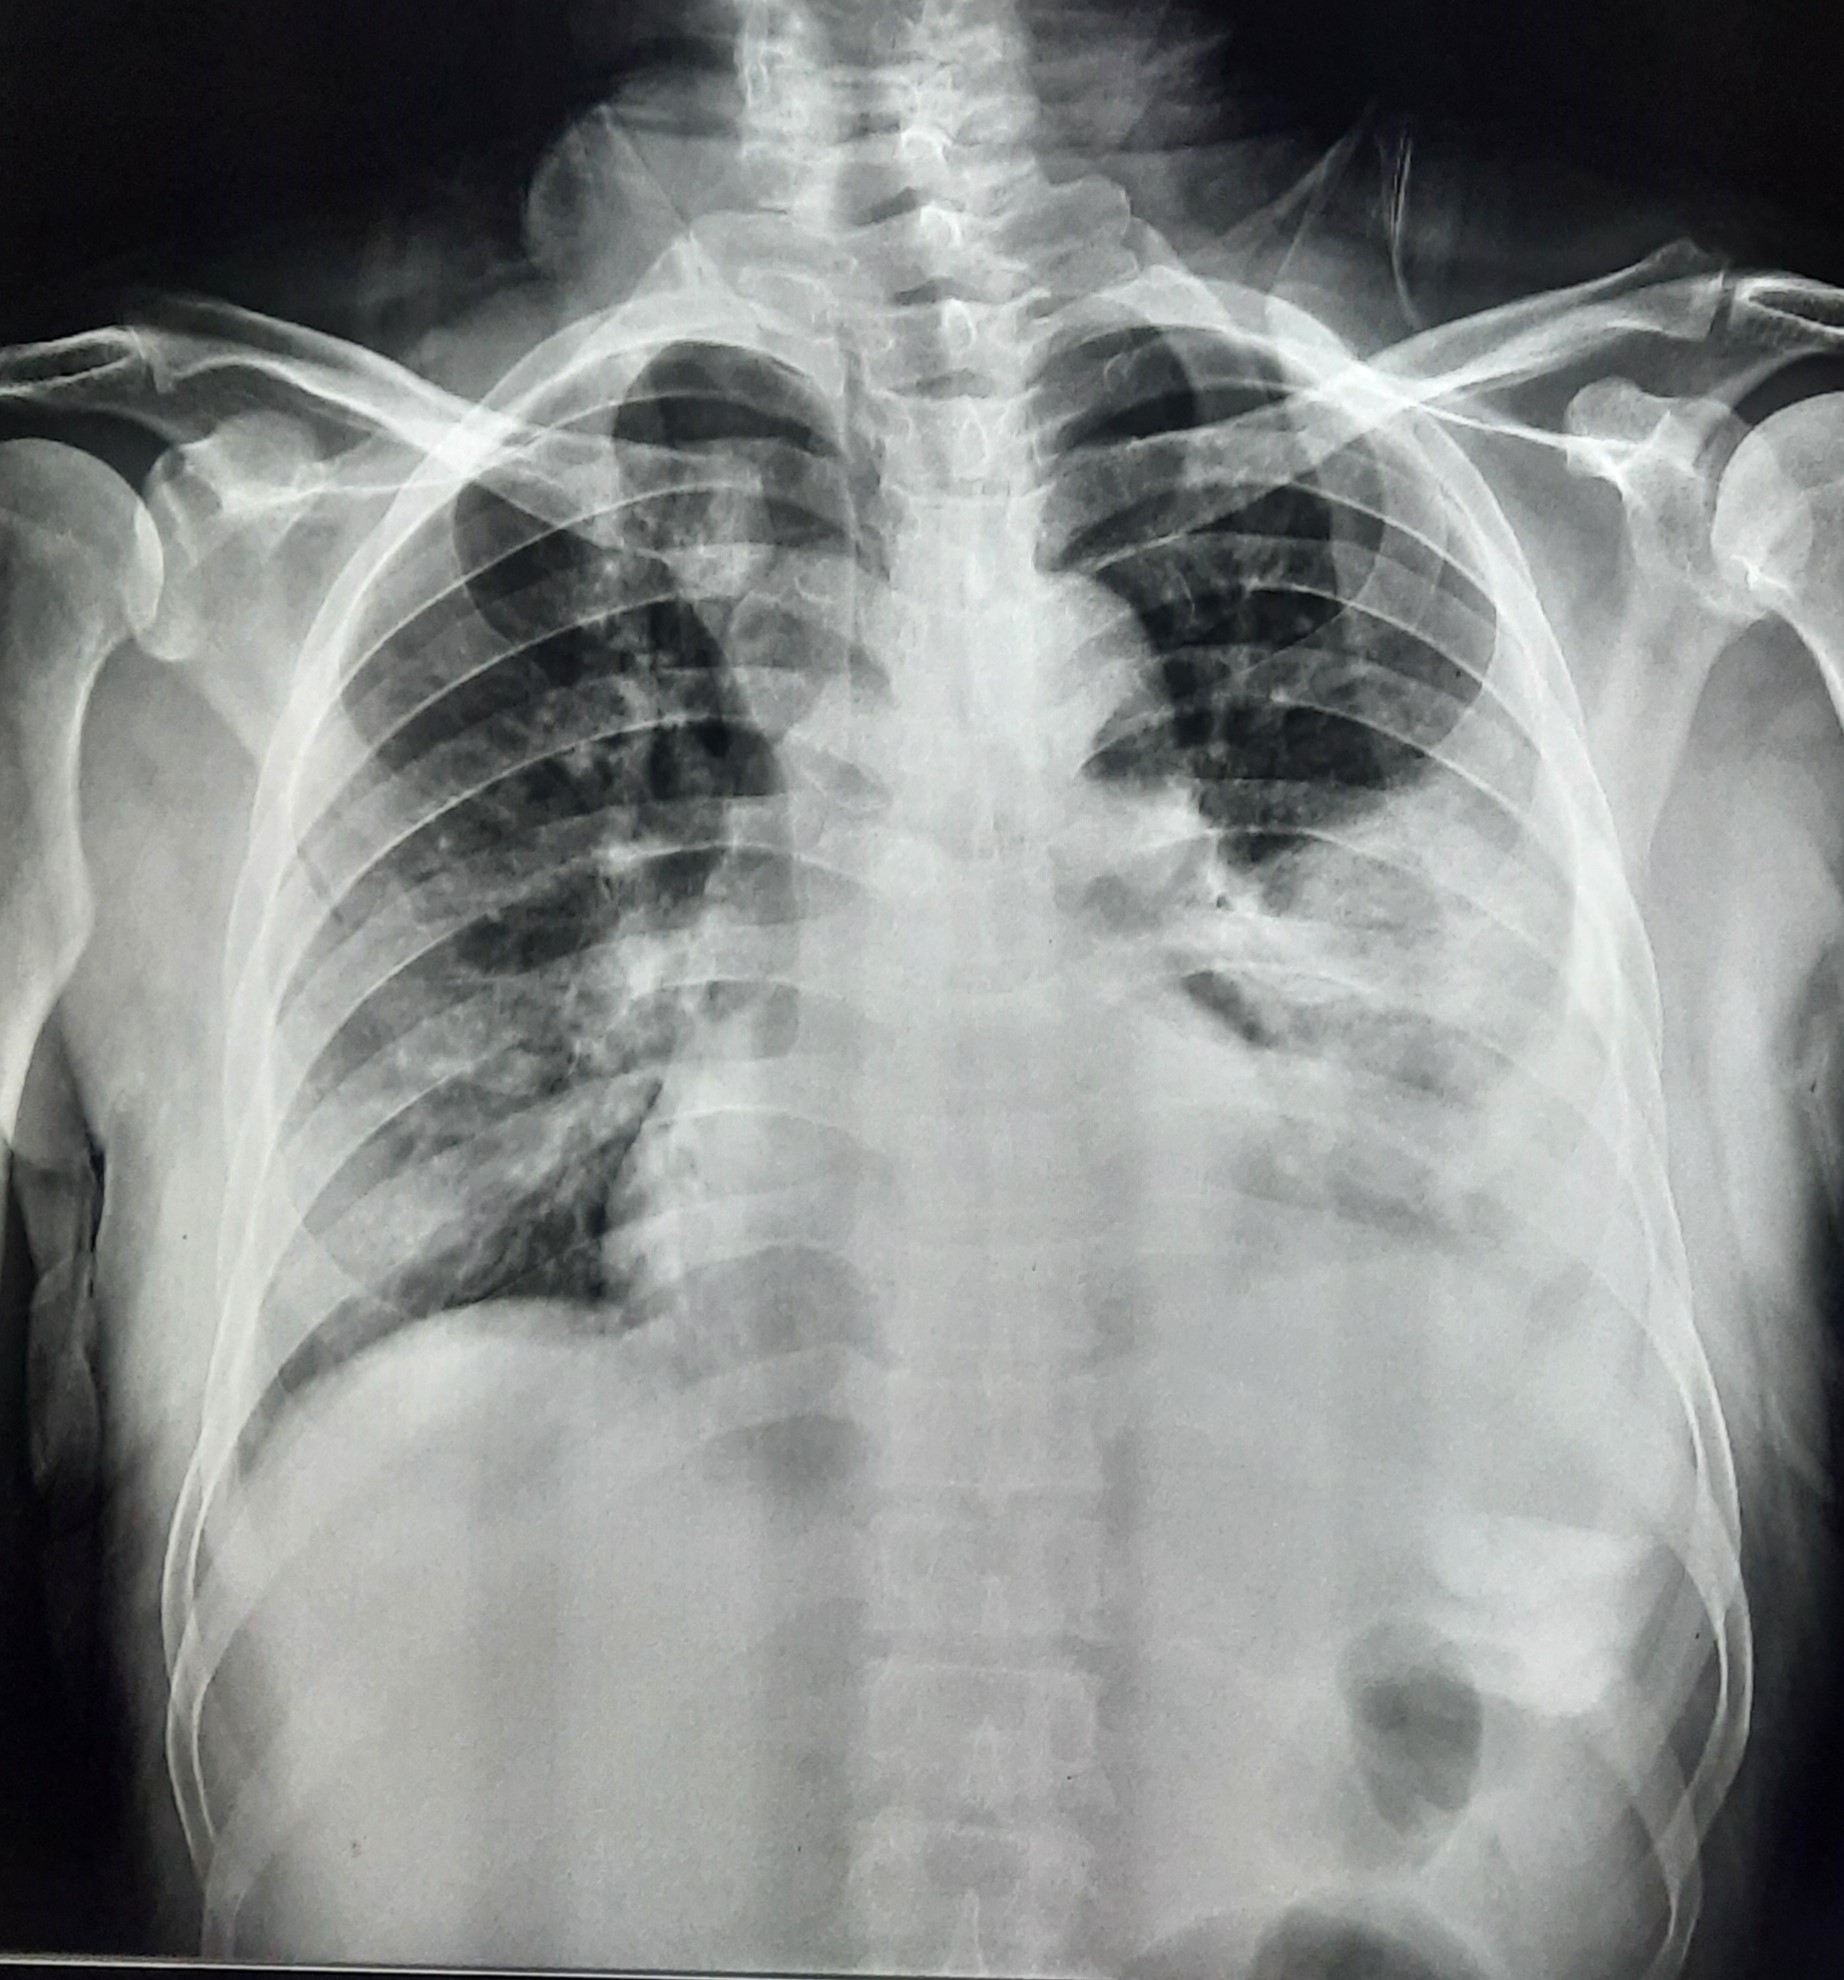

| 102 | IGGMC, Nagpur, Nagpur | P2 | 29-4370 | Prachi Bawane | Consent taken on Paper | 17 Yrs. |

Provisional Diag : PTB?

Final Diag : Active Pulmonary Tuberculosis With Tuberculi? Right Sided Pleural Effusion |

TB Case (Confirmed) | Bilateral ill Defined, No Homogenous Reticulonodular opacities, Right CP Angle Blunting | Abnormality visible on x-ray |